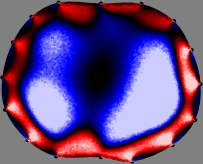

To explain the FER method, we closely examine the correlations among column vectors of the sensitivity matrix , described in Fig. 2. The correlation between and can be expressed as

for [23]. This shows that the column vector is like an EEG (electroencephalography) data induced by dipole sources with directions at locations . Given that two dipole sources at distant locations produce mutually independent data, the correlation between and decreases with the distance between and . Fig. 2 shows a few images of the correlation as a function of for four different positions . The correlation decreases rapidly as the distance increases. In the green regions where the correlation is almost zero, is nearly orthogonal to .

Fig. 2 shows that if and are far from each other, the corresponding columns of the sensitivity matrix are nearly orthogonal. This somewhat orthogonal structure of the sensitivity matrix motivates an algebraic formula that directly computes the local ensemble average of conductivity changes at each point using the inner product between changes in the data and a scaled sensitivity vector at that point: